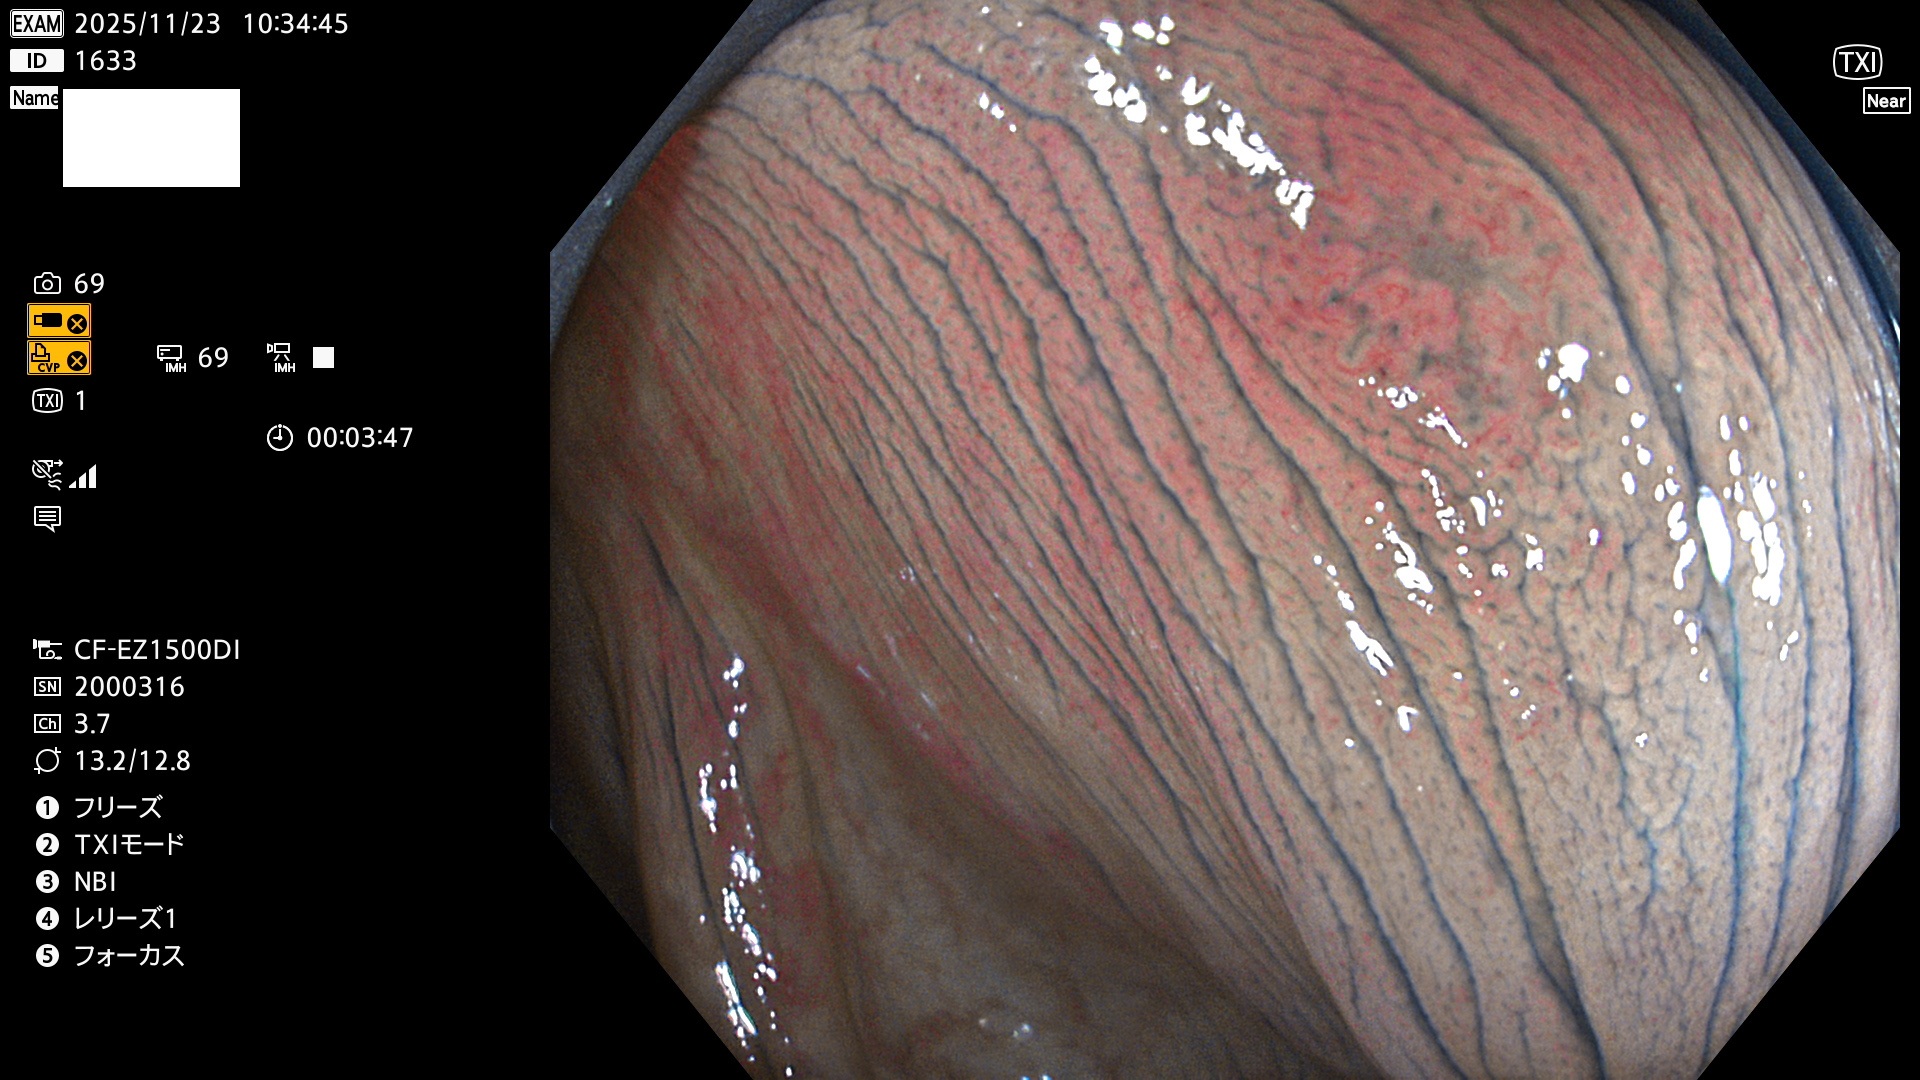

完全に平坦な物をUb、陥凹している物をUcと呼びます。Ubは認識が困難で、Ucはびらん(炎症)と紛らわしいために見落とされやすく、「内視鏡後・大腸癌」の原因になります。

専門的)Uc=De Novo癌? 内視鏡の解像度が低かった時代、このような説もありました。しかし今日の高精度内視鏡では良性の微小なUc型腺腫(APC遺伝子異常の腺腫)が日常的に見つかります。Ucこそが多段階発癌(Adenoma-Carcinoma Sequence)のMain Routeです。

毎週の検査(木・金・土・日)に発見されたUbとUc型・腺腫を、その週の日曜の夜にUPし1週間、提示します。

2025年11月20日〜11月23日の4日間(40件)8個 (Uc_ADR=8個/40人=20%)